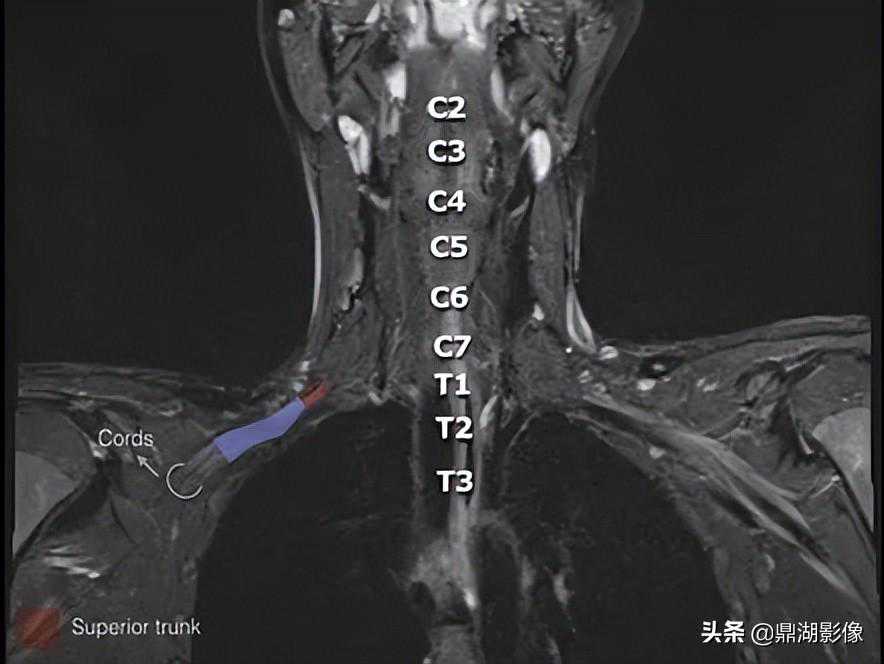

臂丛的MRI解剖图

冠状位